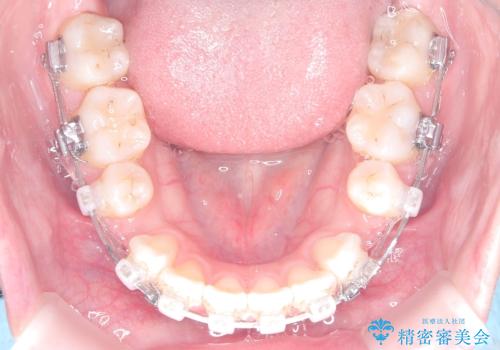

- 審美ワイヤー

精密検査の結果、歯を後方へ下げるためのスペースが不足していたため、上下左右の4番目の歯(第一小臼歯)を計4本抜歯する計画を立案しました。抜歯によってできたスペースを最大限に活用し、前歯を後ろに下げることで、口元のボリュームを抑え、バランスの良いEライン(横顔のライン)を目指すこととしました。装置は、日常生活で目立ちにくい審美ワイヤーを選択しました。

治療は、審美ワイヤーを用いて抜歯スペースを徐々に閉じながら、前歯の角度と位置を精密にコントロールして進められました。ワイヤー矯正は歯を三次元的にしっかりと動かすことができるため、前歯を単に倒すのではなく、根元から理想的な位置へと誘導しました。

1年半の治療期間を経て、抜歯したスペースは完全に閉じ、突き出ていた前歯はすっきりと内側に収まりました。噛み合わせの精度も向上し、機能面でも良好な結果が得られています。